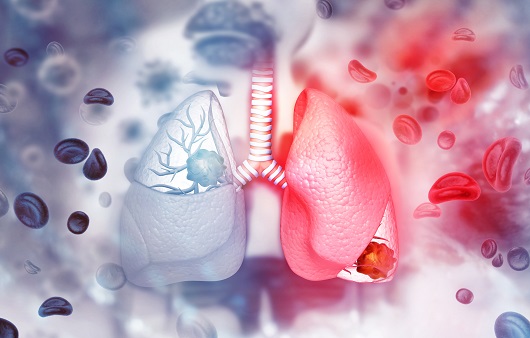

흡연은 폐암의 주요 원인으로 폐암 발생의 약 85%를 차지합니다. 폐암 발병 위험은 흡연한 담배의 개수와 흡연 기간에 따라 달라집니다. 담배를 끊은 사람은 폐암 발병 위험이 낮아지지만, 과거 흡연자는 담배를 피운 적이 없는 사람에 비해 위험이 계속 증가합니다.

흡연 외에도 대기 오염, 마리화나 사용, 담배 연기 및 간접흡연, 난방을 위한 화기 사용으로 인해 석면, 방사선, 라돈, 비소, 크롬산염 등 폐암의 알려진 위험 요인에 노출될 수 있습니다. 폐암, 특히 선암과 기관지 폐포 세포암은 결핵과 같은 다른 폐 질환으로 인한 폐의 흉터로 인해 발생하는 경우도 적지 않습니다.